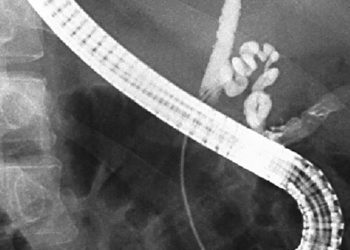

Study Rundown: In 2014, a Consumer Product Safety Commission injunction prevented the sale of high-powered magnet sets, based on an uptick in magnet-associated injuries after the products’ introduction in 2008. Manufacturers won the right to resume distribution in 2016, citing incomplete data regarding the injury risk these products posed to children. Researchers at twenty-five US children’s hospitals participated in a retrospective cohort study to identify children presenting for high-powered magnet exposure between January 2017 and December 2019. 596 patients ranging from 2 months to 18 years were found, with an overwhelming majority seeking care for ingestion of two or more magnets. Of this cohort, approximately half of the cases required endoscopic or surgical intervention, and nearly 10% of patients suffered intestinal perforation, fistula formation, or another significant morbidity. Increases in morbidity risk were found for patients with developmental delay, as well as ingestion of >1 magnet and magnets <5mm in diameter. Though the identification of patients presenting to tertiary centers may overestimate morbidity risk, the large patient population and convincing stratification of risk factors strengthen this first-of-its-kind database of pediatric high-powered magnet exposures. This study’s delineation of multiple facets of these cases – from the imaging-associated radiation exposure to the suspected location of magnet ingestion – provides crucial context for the on-going medico-legal debate regarding the safety of these products.

In-Depth [retrospective cohort]: Twenty-five US children’s hospitals identified charts of patients seen for foreign body ICD-10 codes between 1/1/17 and 12/31/19. Cases of high-powered magnet ingestion were included after manual review and a standardized chart abstraction process. 596 patients, aged 2 months to 18 years, were found. 50% of cases required hospitalization. 46.3% of cases required either endoscopy or surgical intervention, and 9.6% of patients suffered from some form of gastrointestinal morbidity. Risk for morbidity was increased for patients with developmental delay (OR 3.25, 95% CI 1.81-5.85), who presented for care more than once before definitive diagnosis (21.28, 6.84-66.19), and who did not spontaneously pass the magnets (40, 9.6-164). Aside from respiratory distress, all other categorized symptoms on presentation were positively associated with morbidity, with abdominal distension carrying the greatest risk. Magnets <5mm were 7-fold more likely to cause injury (p=0.001). No injury occurred with only one ingested magnet, with 2 magnets and 3+ magnets carrying a 7.5% and 18.7% risk for morbidity, respectively (p<0.001). Sex, race, and ethnicity had no bearing on morbidity risk.